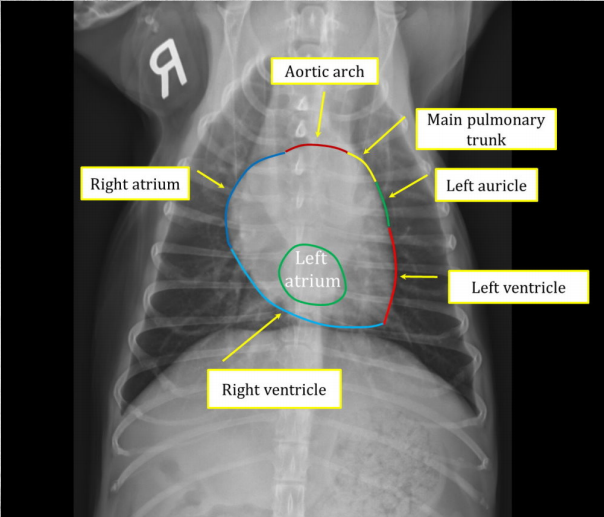

Cardiac silhouettes in dogs. (4)

● "Size is considered normal if no clear abnormalities are seen." ● Distance between base and apex is ca 70% of depth of thorax on lateral view. ● Heart width on LAT view may be 2,5-3,5 intercostal spaces. ● Heart width on VD/DV should not be more than 2/3 of the width of the thorax.

Enlargement of left atrium. in right, VD image, arrows show location of left atrium.